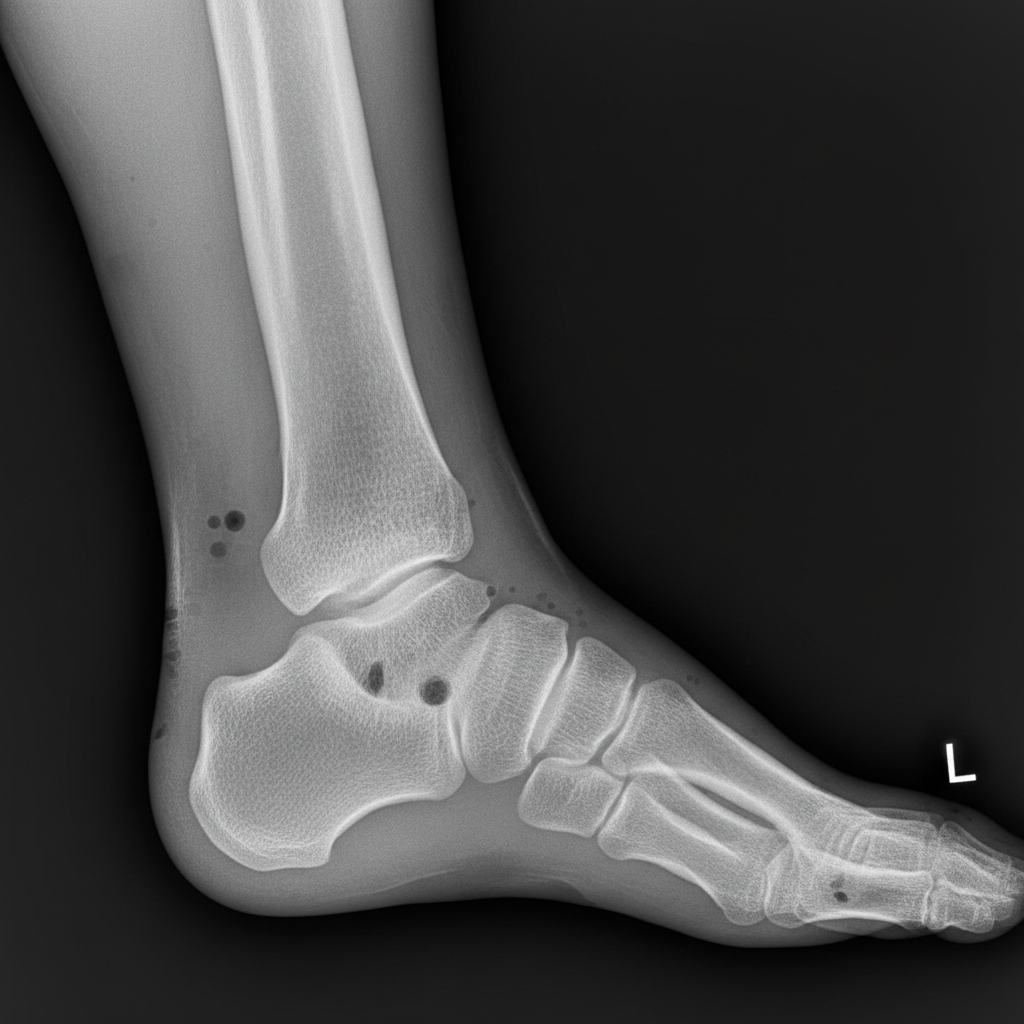

골절 진단서부터 수술 기록지, 입퇴원 기록, 외래 진료 기록, 처방전, 영상 자료(X-ray, MRI 등)까지 모든 의료 기록은 빠짐없이 보관해야 합니다. 이 모든 기록이 외측복사골절 후유장해를 증명하는 핵심적인 증거가 되기 때문이에요. 혹시 모를 상황에 대비해서 사본을 여러 개 만들어두는 것도 좋은 방법이에요. - 전문가와 반드시 상담하세요.